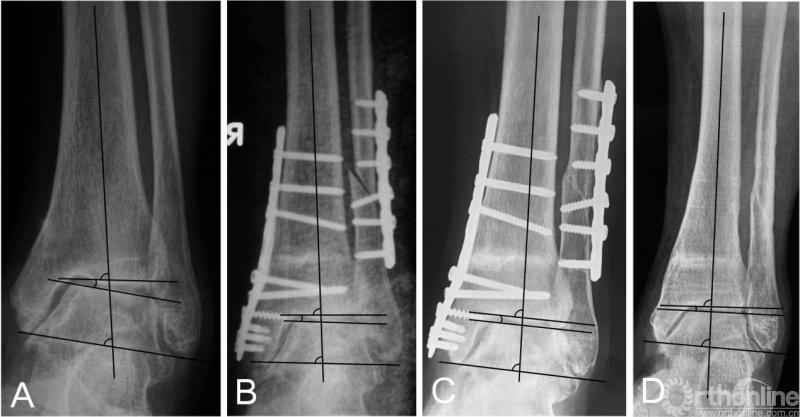

对于内翻型踝关节OA,选择合适的截骨矫形术式可以改善愈后。常用的术式大体分为三类:外侧闭合楔形截骨、内侧开放楔形截骨和关节内(Plafond)截骨术。尽管Stamatis等[19]指出,不同术式的选择并不影响临床及影响学结果,或骨愈合时间。然而,虽然闭合截骨的手术操作相对容易[27],如果患者条件允许,我们更倾向于内侧开放楔形截骨术(图2)。因为外侧闭合截骨术可能导致患者短缩及术后外侧肌力变弱等问题[20],且所有闭合截骨的患者,均需要行腓骨截骨,对于部分患者无疑会增加不必要的创伤[10]。然而,如果存在软组织问题,如局部疤痕形成、早期存在感染、或潜在的血管问题,外侧闭合截骨也是较好的选择[27]。我们在临床上也采用外侧闭合截骨术,但并未纳入本研究。对于胫骨远端关节面内侧部分存在内翻改变,即畸形顶点位于关节面时,踝上结果并不能纠正关节内畸形,此时可采用Plafond截骨术[15]。近期,Ahn等[6]报道了一种保留腓骨的胫骨远端截骨术,截骨线从踝上5 cm斜向外下至踝上5 mm,主要针对伴有距骨内移及踝穴增宽的内翻型踝关节骨关节炎。

图2 患者为52岁女性,术前X线提示为Takakura-3A期踝关节骨关节炎(2A);行踝上截骨合并腓骨截骨,术后关节面匹配度及负重力线均得到矫正(2B);术后12个月及47个月的随访提示矫形效果得到维持,改良Takakura分期降至1期。